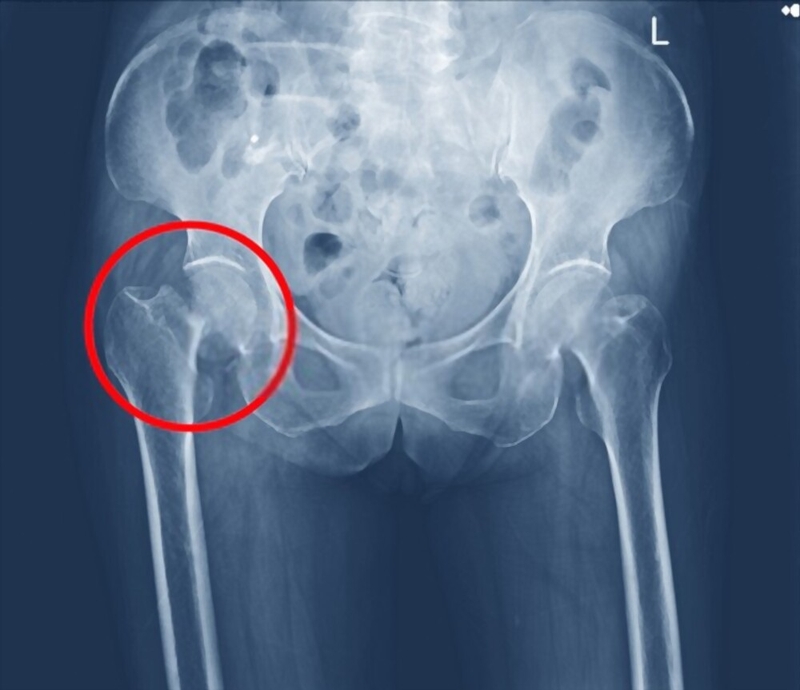

Gãy xương cổ đùi là một dạng gãy xương thường gặp ở vùng khớp háng. Đối với người cao tuổi, gãy xương cổ đùi thường xảy ra do tình trạng loãng xương sau một chấn thương đơn giản như té ngã.

Người cao tuổi thường gặp những tai nạn sinh hoạt như trượt ngã trên sàn nhà trơn hoặc té ngã từ ghế, võng xuống đất. Kết quả là gãy xương cổ đùi xảy ra, và thường yêu cầu phẫu thuật cho phần trên của chi, đặc biệt là phẫu thuật thay khớp háng ở người già. Nếu té ngã và bị đập vào bên hông khi tiếp đất, thì thường sẽ gãy xương cổ đùi cho phần dưới của chi.